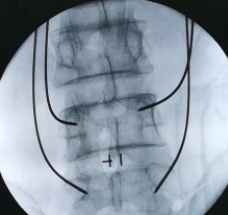

术中

这时候再结合骨科机器人,根据术前规划路径,自动调节进针角度、分析确定定位点,并智能自动寻找。在骨科机器人的帮助下,医生只需在置钉部位切开约2cm切口,这样不损伤其它椎关节,保障了神经安全,使手术更精准、更微创、患者更快康复。

在骨科机器人+3D裸眼显微镜的辅助下,王阿姨的手术进行的很顺利,术中仅出血约50ml,而皮肤表面也只留下了3cm的小切口,这一切都与传统手术形成的极大对比!可以说,骨科机器人+3D裸眼显微镜在当今脊柱外科关于微创手术这一概念中,已成为一种趋势,其最大程度的保证了患者在术中的安全,将微创手术最为核心的精准、伤害小的特点发挥的淋漓尽致,这对于患者本身及术后的康复来说都极为有利!